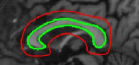

5.3 Elliptical templates

Many of the bio-medical cells can be approximated with an ellipse [14]. We present results using two elliptical shaped templates: a spline synthesized ellipse for which we use the partial derivatives given in equations (36) and (41) directly, an exact ellipse for which we use the parameterization given in [16] and use the equation (26). First row of Figure 8 corresponds to a hand drawn ellipse and the second row correspond to a parametric ellipse. We considered these two parameterizations to show that the algorithm performance is not critically dependent on the parameterization. These are fundus images taken from [32]. The presence of veins in the fundus anatomy obscures snakes whose energies rely on image derivative functions. From the results shown in Figure 8, we infer that the proposed technique is less affected by the vein structures or the parameterization and captures the near elliptical shape of the fundus outline.